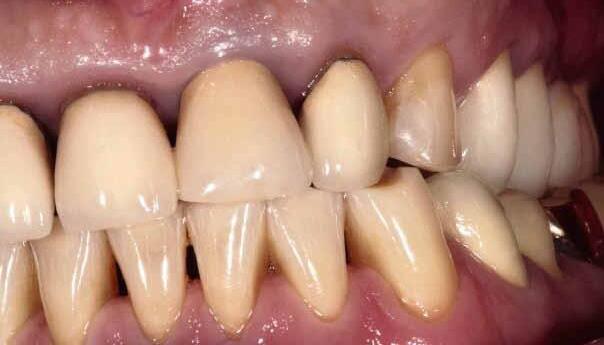

A significant number of people are unhappy with their smile, which has a considerable psychosocial impact. Although many seek cosmetic dental treatment, costs, fear and duration of total treatment are often barriers to the patients. Nevertheless, many could benefit from small and subtle changes to their teeth. With simple direct and freehand techniques, quick but significant results can be obtained that ultimately greatly improve the overall smile aesthetics.

The restoration of abfractions in the anterior area is important for aesthetic appearance especially in patients with high smile lines. Moreover, restoring abfractions strengthens the cervical area of the tooth, prevents further loss of enamel and ameliorates unpleasant sensitivity.

Black triangles and diastemas can cause entrapment of the food and accumulation of bacteria, which leads to gingivitis and ultimately periodontitis. By eliminating the black triangles and diastemas with composite bonding, the dentist not only improves the aesthetics, but also protects the long-term health of the periodontal tissues.

Worn canine cusp restoration is of special functional importance. Creating functional canine guidance with a minimally invasive composite addition to the canine cusp will protect the posterior teeth during lateral movements of the jaw. Incisal wear restorations return the youthful appearance to the smile and prevent further loss of enamel and exposure of the dentinee.